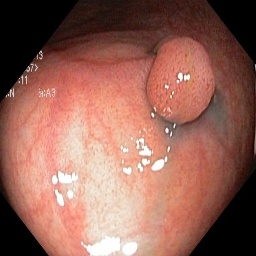

(a) Refer to caption Refer to caption Refer to caption Refer to caption Refer to caption Refer to caption

(b) Refer to caption Refer to caption Refer to caption Refer to caption Refer to caption Refer to caption

(c) Refer to caption Refer to caption Refer to caption Refer to caption Refer to caption Refer to caption

(d) Refer to caption Refer to caption Refer to caption Refer to caption Refer to caption Refer to caption

(e) Refer to caption Refer to caption Refer to caption Refer to caption Refer to caption Refer to caption

(f) Refer to caption Refer to caption Refer to caption Refer to caption Refer to caption Refer to caption

(g) Refer to caption Refer to caption Refer to caption Refer to caption Refer to caption Refer to caption

(h) Refer to caption Refer to caption Refer to caption Refer to caption Refer to caption Refer to caption

Figure 3: Sample data used and generated in the different steps of PolypConnect pipeline. (a) - real polyp images, (b) - manually annotated polyp masks, (c) - randomly selected colon images used as input to the final step of PolypConnect, (d) - extracted edge images of row c. (e) - extracted edge images of polyp regions of row a using the masks of row b. (f) - combined edge images of row d and f. (g) - generated polyp on the images of row c using EdgeConnect. (h) - generated samples from AOTGAN.